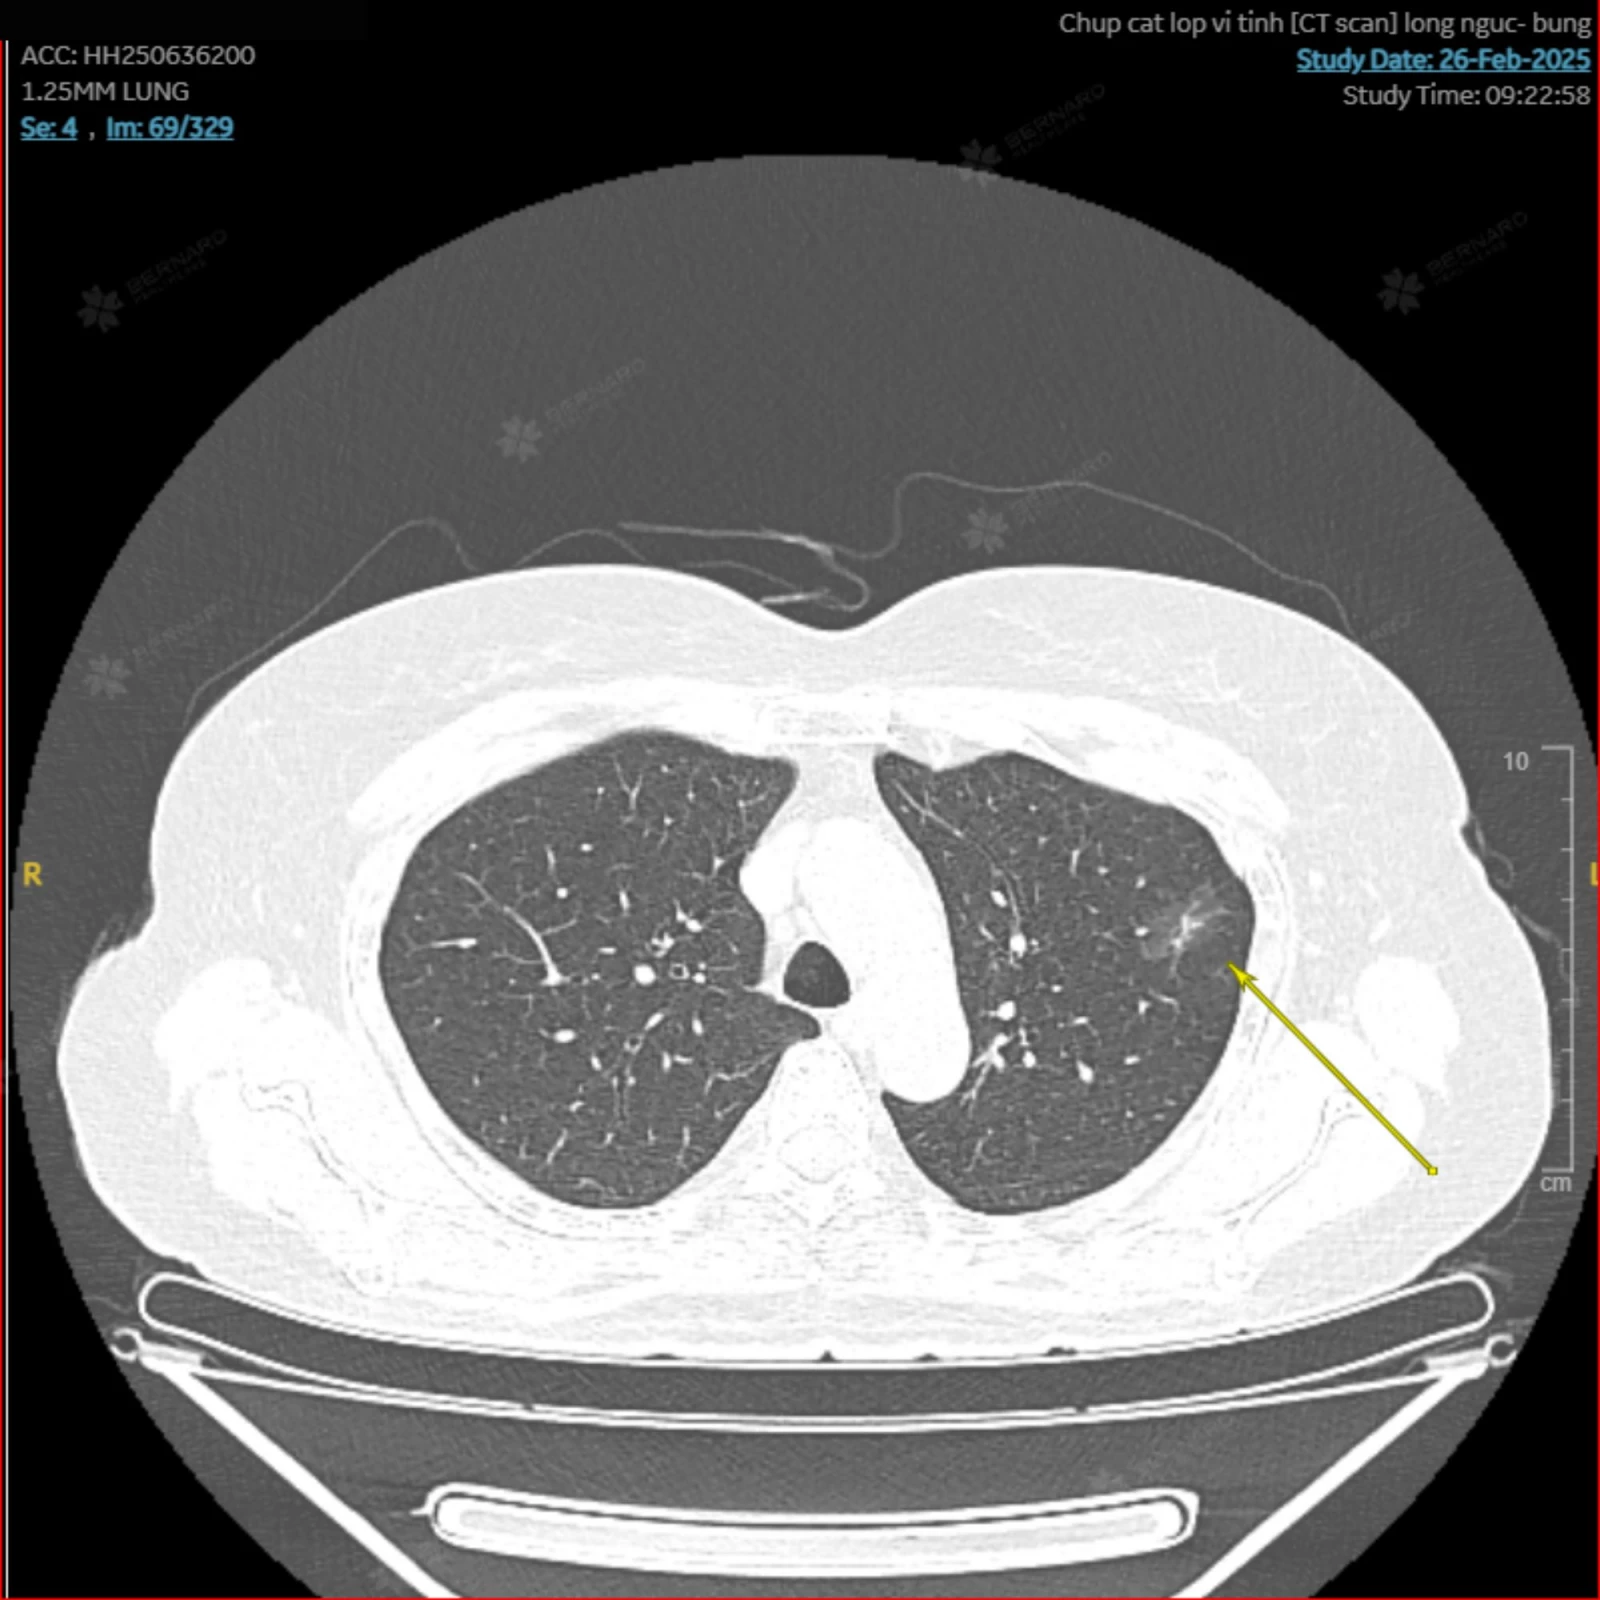

Qua ảnh chụp CT Scan, bác sĩ Bernard phát hiện hai tổn thương, nằm tại phổi trái. Cụ thể, một tổn thương kính mờ tại S3, kích thước 1.1 x 2cm và một tổn thương nốt mờ tại S1-2, kích thước 4mm - Đây là tổn thương rất nhỏ và dễ bị bỏ sót trên X-quang thông thường. Kết quả dấu ấn sinh học CYFRA 21-1 còn cho thấy nồng độ 7,61 ng/mL, cao hơn so với giá trị bình thường (<3,3 ng/mL), gợi ý nguy cơ bất thường ở phổi.

Sau 2 lớp phân tích tỉ mỉ, chuyên gia Nhật Bản kết luận: “Có tồn tại một tổn thương kính mờ bán đặc 23 mm tại thùy trên phổi trái (S1+2), với phần đặc khoảng 5 mm – nghi ngờ ung thư biểu mô tuyến xâm lấn tối thiểu (cT1mi). Ngoài ra, nốt kính mờ 5 mm còn lại có thể là tăng sản tuyến không điển hình (atypical adenomatous hyperplasia) hoặc ung thư biểu mô tuyến tại chỗ (adenocarcinoma in situ). Đây là những tổn thương thuộc phổ ung thư biểu mô tuyến phổi giai đoạn rất sớm, tiên lượng điều trị tốt nếu được can thiệp kịp thời”.